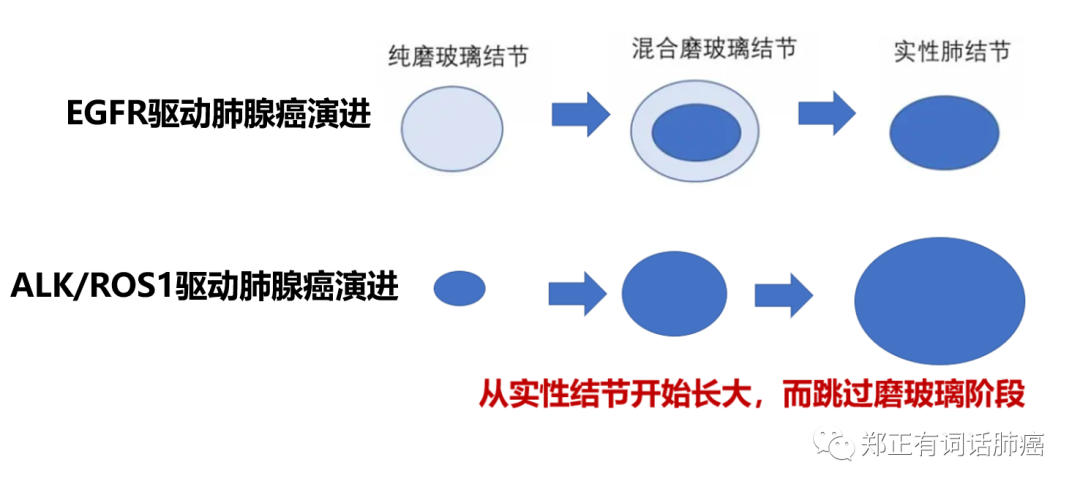

和ROS-1、ALK等驱动基因不一样的是,EGFR驱动肺癌一般都经历磨玻璃阶段。

所以,更好地评价EGFR驱动对预后的影响,我们需要基于肺癌的不同阶段进行分类解读,早期如何,分期偏晚又如何。

从影像层面而言,在磨玻璃尚存的情况下,肿瘤侵袭性较弱,EGFR应该很难发挥功效,而一旦转变为纯实性的状态,其可能会对肿瘤预后产生影响。